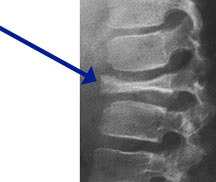

- Radiographically variable appearance: may appear benign (geographic) or malignant (permeative or moth eaten)

- Vertebral plana is braced and observed